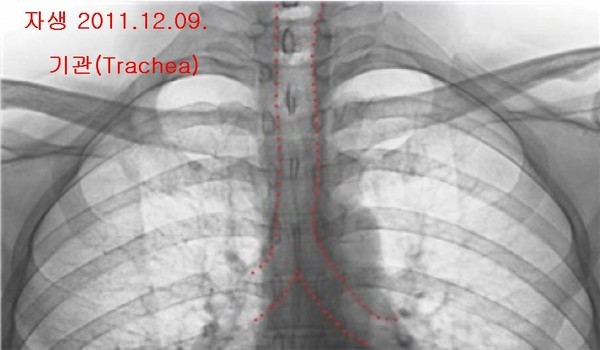

- ▲ 양승오 박사 재판 피고인들이, 유력한 증거로 꼽고 있는 박주신씨 명의의 엑스레이 3장. 왼쪽부터 공군훈련소(2011년 8월 촬영)-자생병원(2011년 12월 촬영)-비자발급용 엑스레이(2014년 7월 촬영). ⓒ 뉴데일리DB

박주신씨의 신체를 촬영한 것으로 알려진 엑스레이는 모두 3장이 있다. 이 중, ‘공군훈련소 입소 당시 엑스레이’(촬영일자 2011년 8월 30일, 이하 공군 엑스레이)와, 주신씨가 ‘비자발급을 위해 촬영한 세브란스병원 엑스레이’(촬영일자 2014년 7월 31일, 이하 비자발급용 엑스레이)는 피고인들도 박주신씨 본인의 것으로 보고 있다.

반면 피고인들은, 박주신씨가 병역처분 변경을 위해 병무청에 제출한 자생병원 엑스레이(촬영일자 2011년 12월 9일)는, 주신씨가 아닌 대리신검자의 것으로 의심하고 있다.

양승오 박사는 “공군에서 찍은 엑스레이와 비자발급을 위해 찍은 엑스레이에서는 피사체의 제1흉추와 제7경추 극상돌기가 오른쪽으로 휘어있지만, 자생병원에서 찍은 영상에서는 정방향으로 나온다”며, “이 2개만 가지고도 동일인으로 볼 수 없다”는 소견을 밝혔다.

이어 양 박사는 박주신씨 명의 엑스레이 3장에서 공군-비자발급용 엑스레이와 달리 자생병원 엑스레이에서만, 기관(氣管)의 모양이 다른 점, 흉곽의 좌우 길이가 더 긴 점 등을 근거로 들며, 피사체를 동일인으로 볼 수 없다는 의견을 나타냈다.

- ▲ 박주신씨 명의 엑스레이 3장에서 나타나는 기관(氣管)의 주행 형태. 자생병원 엑스레이는 직선으로 뻗어 있으나, 공군-비자발급용 엑스레이는 왼쪽으로 휘어있다. ⓒ 의료혁신투쟁위 제공